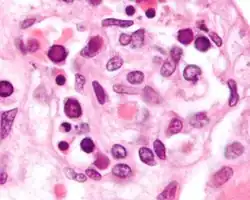

![]() | |

| 16-month-old with erythema infectiosum, displaying characteristic red rashes | |